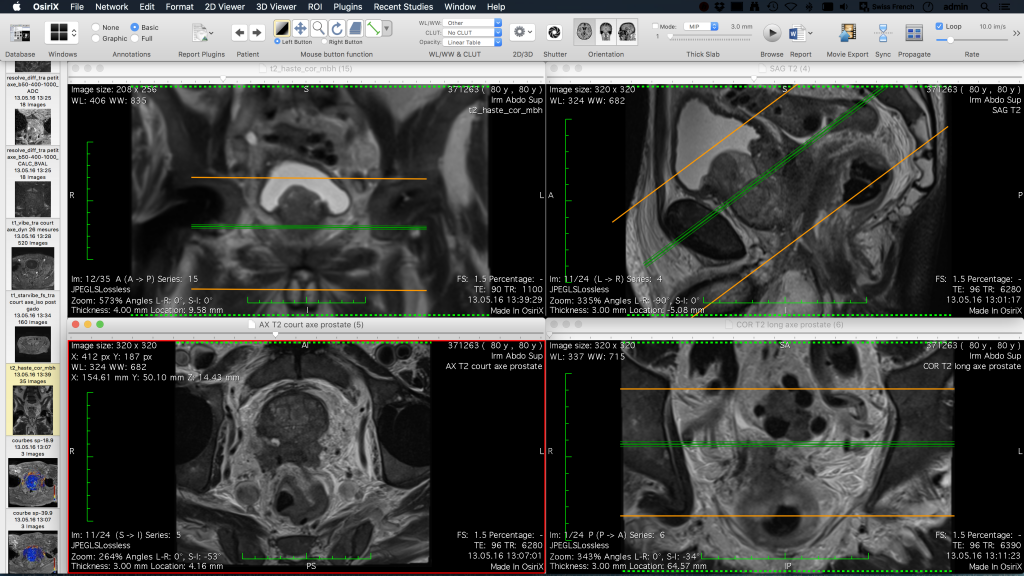

Visor imágenes

Accede a las imágenes DICOM desde la aplicación ya que está integrada con nuestra solución de servidor PACS.

Medical Sinerkia se integra con un visor DICOM para tener en una única herramienta toda la información del paciente.

DICOM

Medical Sinerkia permite la integración con un visor de imágenes DICOM para tener toda la información de los pacientes relacionada.